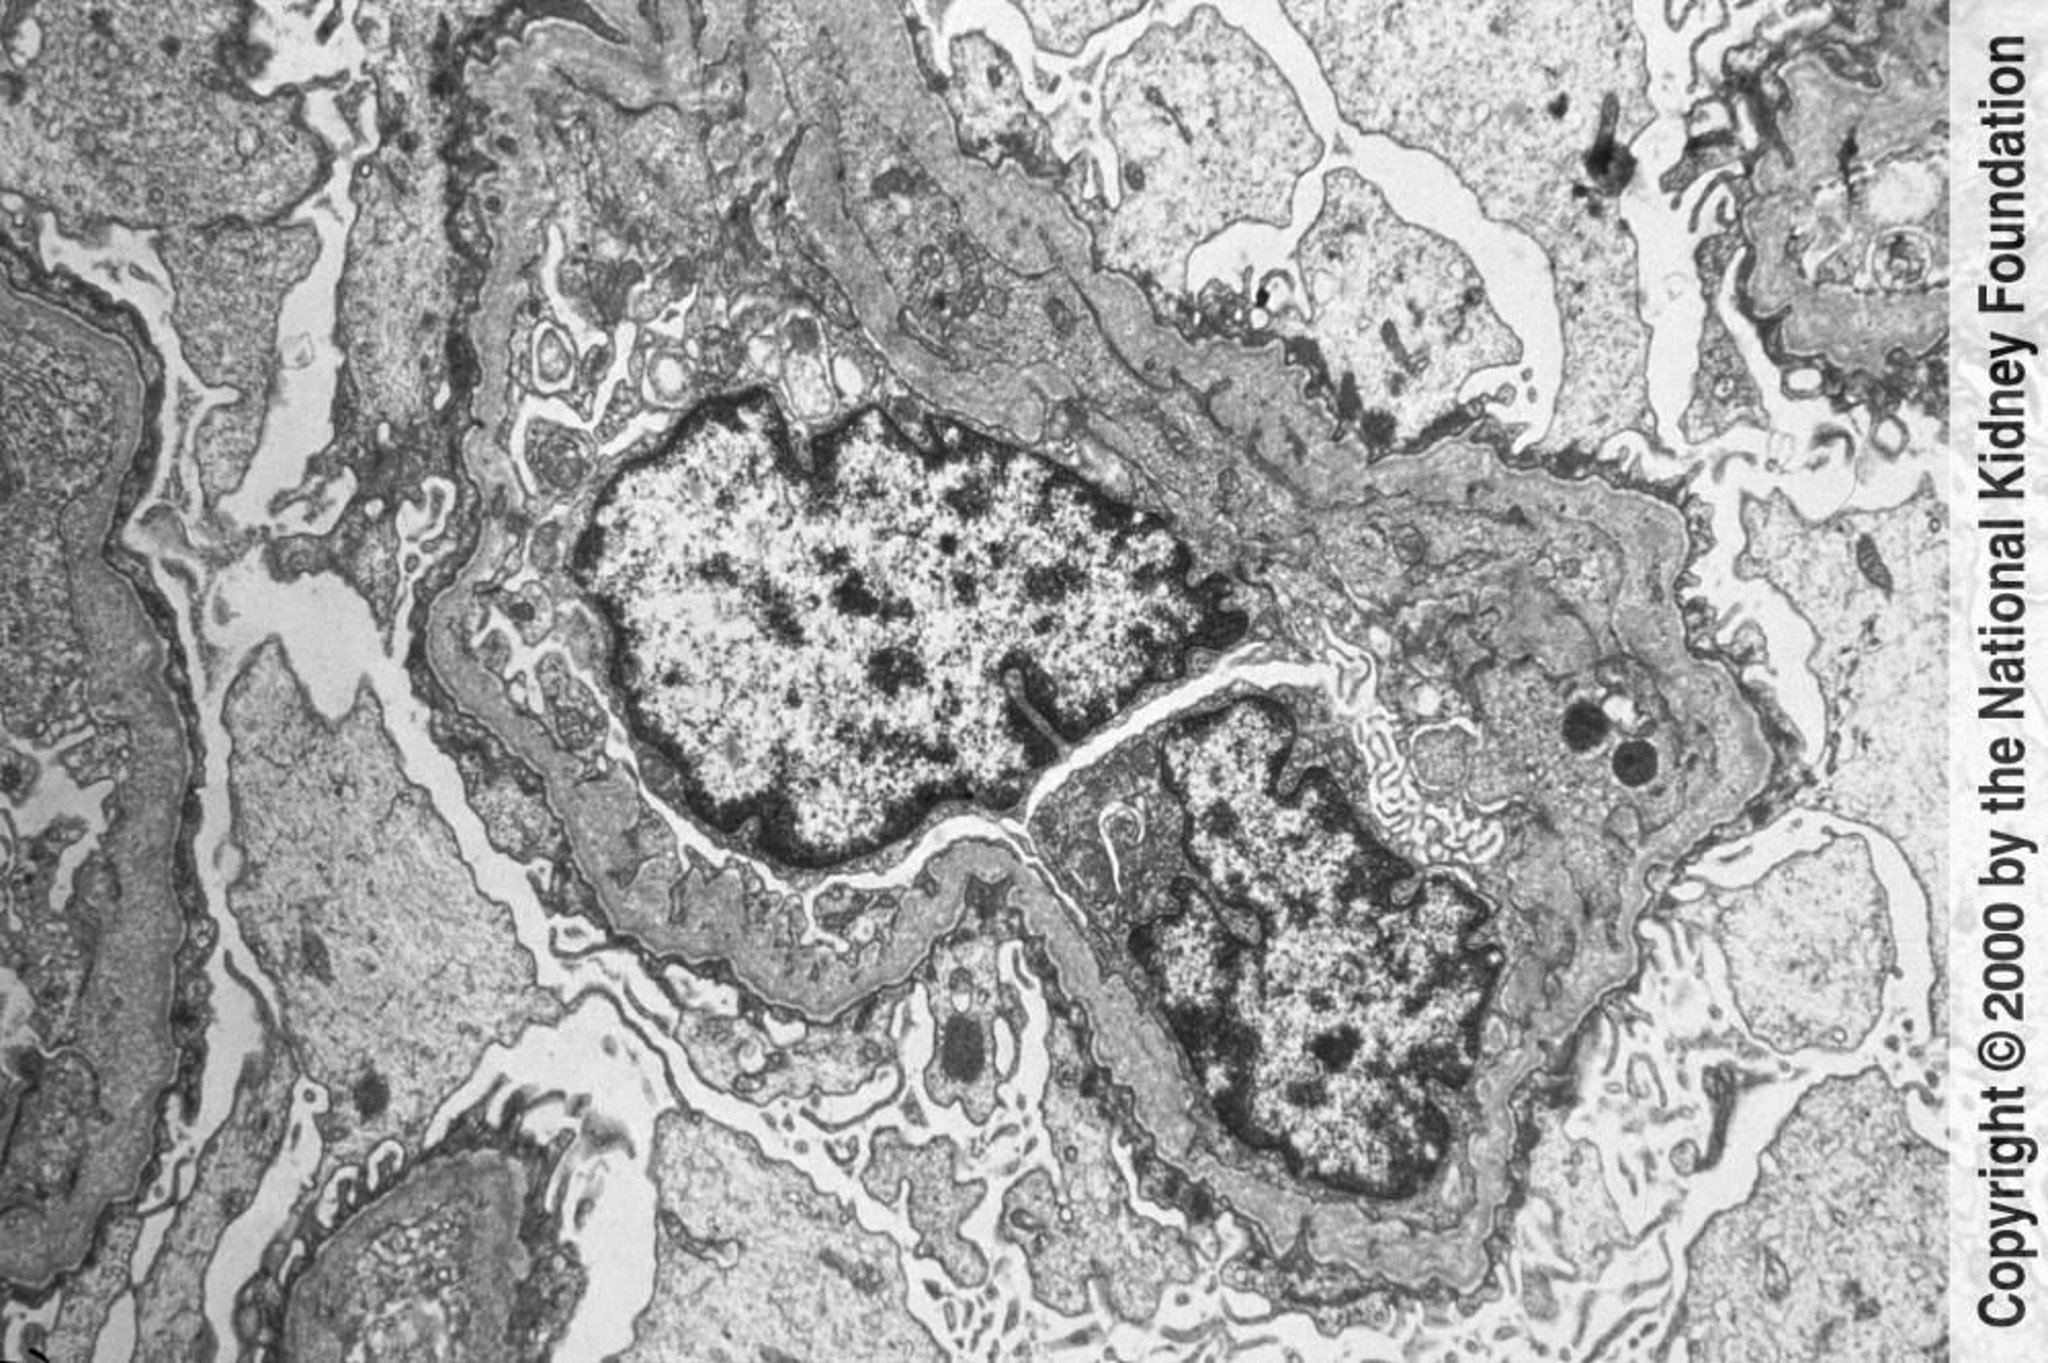

Hội chứng Alport (viêm thận di truyền)

Màng đáy cầu thận mỏng và dày không đều có những lỗ thủng được quan sát thấy dưới kính hiển vi. Những thay đổi gây ra bởi chấn thương và sự tái cấu trúc (×6000).

Hình ảnh do bác sĩ Agnes Fogo và American Journal of Kidney Diseases' Atlas of Renal Pathology cung cấp (xem www.ajkd.org).